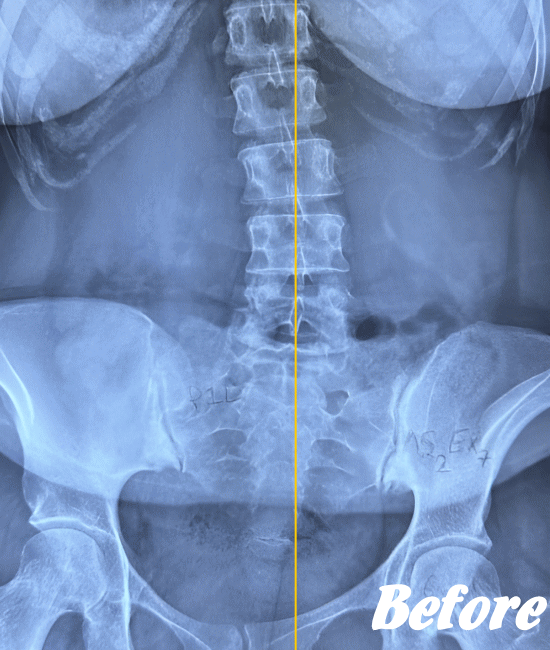

医療機関でも用いられているAKA療法を取り入れた施術により、身体に無理をかけず、ゆっくりと骨や関節の位置を解剖学的に正しい位置へ調整することで、痛みを取り除いていきます。慢性化した痛みも改善します。

多くの場合、骨盤の仙腸関節、腰の骨(腰椎)、そして足の付け根の股関節を調整すれば、痛みはなくなり、健康な状態に回復します。

ぎっくり腰程度であれば、初回の施術で腰が伸ばせる程度までには回復し、2回目の施術で残った痛みを取り除き、3回目で最後の違和感を解消します。